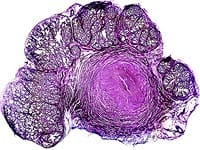

The African cherry tree, pygeum africanum, is an evergreen found at higher elevations across Africa. Its medicinal use dates to the 1700s, when tribes in southern Africa taught early explorers how to use the tree’s bark to treat bladder discomfort.1 Pygeum extract has been used in Europe to treat benign prostatic hyperplasia since the 1960s, and is currently the most commonly used therapeutic for this condition in France.2 Benign prostatic hyperplasia affects approximately 50% of men aged 51-60, and up to 90% of men over the age of 80. This condition causes the prostate gland to enlarge, constricting the urethra and making it difficult for the bladder to empty. Symptoms include reduced urine stream, frequent urination (especially at night), urinary urgency, leaking, and urinary retention. Severe benign prostatic hyperplasia can have serious long-term health effects, such as urinary tract infection, bladder or kidney damage, bladder stones, pain during sexual intercourse, and incontinence. Therapies to treat this condition include pharmaceutical drugs such as Proscar®, Hytrin®, and Flomax®, as well as non-surgical and surgical options. However, all of these remedies have associated side effects. Clinical studies suggest that pygeum bark extract is effective in reducing symptoms of benign prostatic hyperplasia, with few side effects.3,4 Benign prostatic hyperplasia’s cause is not fully known or understood. One theory is that the conversion of testosterone to dihydrotestosterone via the enzyme 5-alpha-reductase contributes to prostate enlargement.5 In addition, as men age, they often experience an increase in levels of estrogen relative to testosterone, indicating that estrogen may be involved in the development of this condition. In one study, extracts of pygeum and nettle root partially blocked the action of two enzymes, aromatase and 5-alpha-reductase, that are involved in the production of estrogen and dihydrotestosterone, respectively. Pygeum showed much higher efficacy at lower doses than did nettle root, but the combination of both herbs was significantly more effective than either alone in blocking the aromatase enzyme.6 How Does Pygeum Work?Pygeum bark contains numerous beneficial constituents, including phytosterols such as beta-sitosterols, which exhibit anti-inflammatory action by inhibiting the production of prostaglandins in the prostate. Other pygeum components in-clude ferulic esters, which reduce levels of prolactin (a hormone that promotes testosterone uptake in the prostate gland), and pentacyclic triterpenes, which inhibit an enzyme involved in inflammation and help reduce edema. Scientists believe that these phytochemicals work together to help counteract the structural and biochemical changes associated with benign prostatic hyperplasia.1,7 Pygeum may help to prevent the overgrowth of prostate cells that can contribute to benign prostatic hyperplasia. Research suggests that pygeum may do this by inhibiting basic fibroblast growth factor, a signaling biochemical involved in the development of benign prostatic hyperplasia.8 In a laboratory study, pygeum extract demonstrated an anti-proliferative effect on prostate cells derived from rats, which was in part mediated by inhibition of basic fibroblast growth factor.9

Enlargement of the prostate gland can obstruct bladder emptying, which can lead to cellular and functional changes in the bladder tissue. Studies of rabbits suggest that pre-treatment with pygeum helps to protect the bladder from developing contractile and biochemical dysfunctions induced by partial bladder outlet obstruction, possibly by protecting the bladder from ischemic injury.10,11 The investigators suggest that pygeum may work in both rabbits and humans to protect the bladder’s smooth muscle against cellular damage induced by obstructed flow.10 Reducing BPH SymptomsClinical trials suggest that pygeum can safely and effectively help to reduce the symptoms of benign prostatic hyperplasia. In a multicenter trial in Europe, 85 men with mild to moderate benign prostatic hyperplasia were given 50 mg of pygeum twice daily for two months. The study participants demonstrated a 40% decrease in the International Prostate Symptom Score, a subjective assessment of the severity of symptoms of benign prostatic hyperplasia. Furthermore, the pygeum-supplemented men reported a 32% decrease in frequency of nocturnal urination (nocturia) and a 31% improvement in quality of life. After the supplementation with pygeum ended, the patients were followed for one additional month. The benefits derived from the pygeum therapy continued even during this period without treatment, indicating a lasting therapeutic effect.12 In a larger placebo-controlled, double-blind study, 263 men received either 100 mg of pygeum or placebo daily for 60 days. The pygeum group demonstrated a 17.2% improvement in urinary flow, a 24.5% decrease in residual bladder volume, a 31% decrease in nocturia, and a 19.4% decrease in daytime urinary frequency. Overall, 66% of the pygeum group reported improvement, compared to only 31% of the placebo group.13 According to two separateliterature reviews, pygeum extract demonstrates statistically significant benefits for benign prostatic hyperplasia. The more recent review, conducted in 2000, analyzed studies dating from 1966 to 2000. In 18 randomized trials involving 1,562 men, pygeum provided significant improvement in combined outcome of urological symptoms and flow measures. Furthermore, men taking pygeum reported twice as much improvement in overall symptoms.3 An earlier literature review published in 1995 examined 12 clinical, placebo-controlled, double-blind studies, in which 358 patients received pygeum and 359 received placebo. Again, those consuming pygeum demonstrated statistically significant benefits compared to those receiving placebo.4

Additional Benefits of PygeumPygeum has also been used to treat inflammation of the prostate, or prostatitis. Prostatitis can occur due to infectious or non-infectious causes, and may cause symptoms such as urinary frequency, urgency, or pain. In a clinical trial, 47 patients with chronic prostatitis received 100 mg of pygeum daily for five to seven weeks. Eighty-nine percent reported a complete remission of symptoms.4 In another study, men with sexual dysfunction due to either benign prostatic hyperplasia or chronic prostatitis received pygeum extract (200 mg daily for 60 days) either alone or with anti-biotics. The men receiving pygeum bark extract experienced improved sexual function, even though there were no significant differences between hormone levels or nocturnal penile rigidity before and after therapy. Based on their findings, the researchers believe that pygeum may be beneficial to patients with sexual or reproductive dysfunction.14